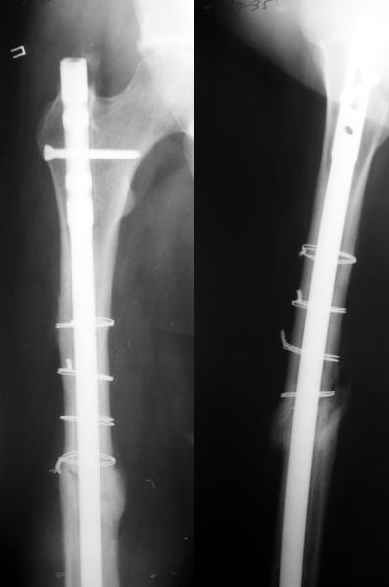

Еще один пример - несращение через полгода после несостоятельного остеосинтеза, и через полгода после реостеосинтеза с блокированием.

1

2